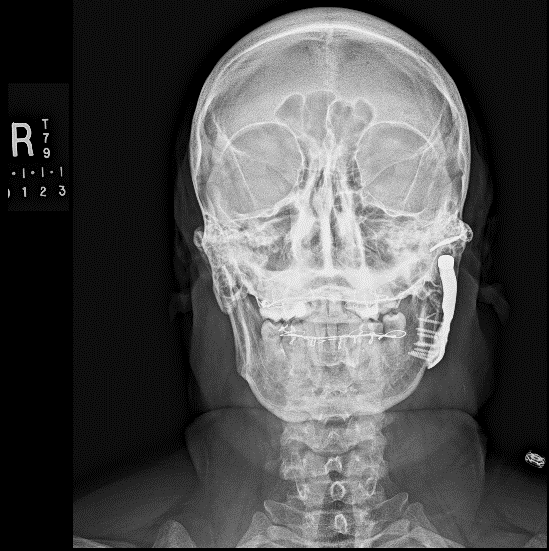

Joint replacement is a significant operation for symptomatic irreparably damaged joints. Costochondral rib graft (see Figure 7) or customised prosthetic joints are used. The unpredictability of costochondral rib (a third are stable, a third resorb and a third overgrow) and refinements to customised prostheses have moved almost all jaw joint replacement for terminal joint damage to these devices (see Figure 8).

Figure 8: Customized total TMJ replacement.